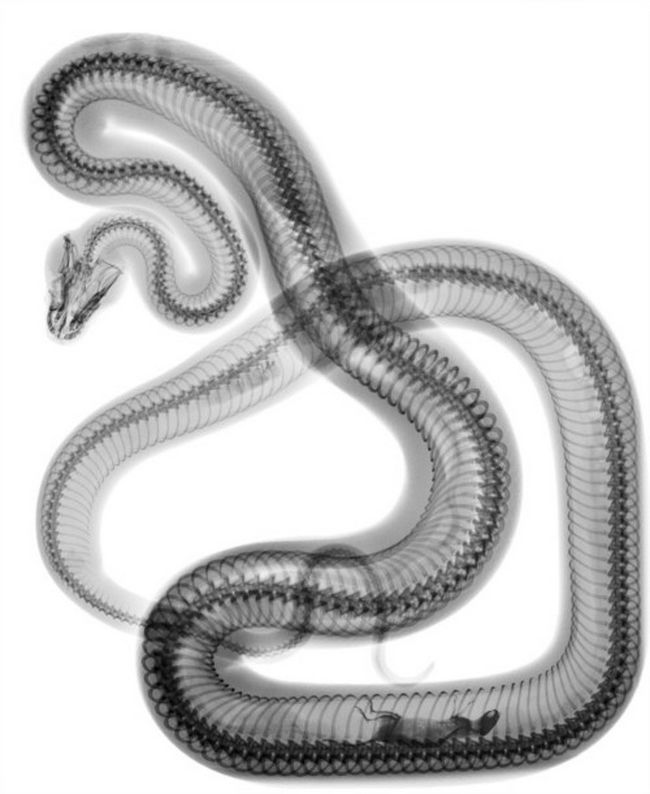

5 – Raio X de uma cobra após o jantar